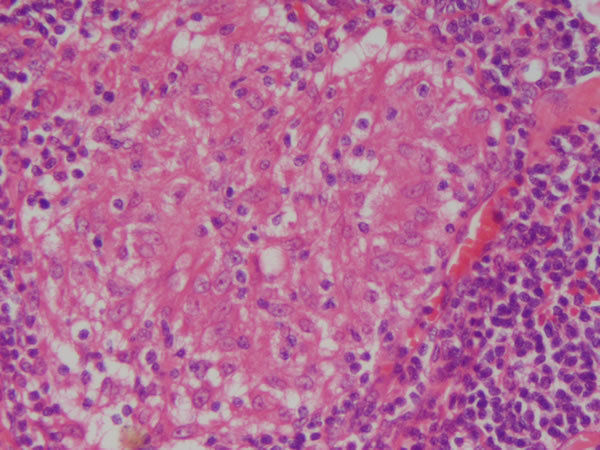

Coração - Tecido Muscular estriado Necrose de coagulação - Infarto Miocárdio Você tbm encontra: maior eosinofilia, degeneração, acúmulo de lipofucsina, hemorragia, leucócitos Causas: Hipóxia, isquemia |

IAM - depleção de ATP, isquemia prolongada, lesão mitocondrial,acúmulo de radicais livres, defeitos na permeabilidade de membranas. |

Coração - Tecido Muscular estriado Necrose de coagulação - IAM Você tbm encontra: maior eosinofilia, degeneração, acúmulo de lipofucsina, hemorragia, leucócitos Causas: hipóxia, isquemia |